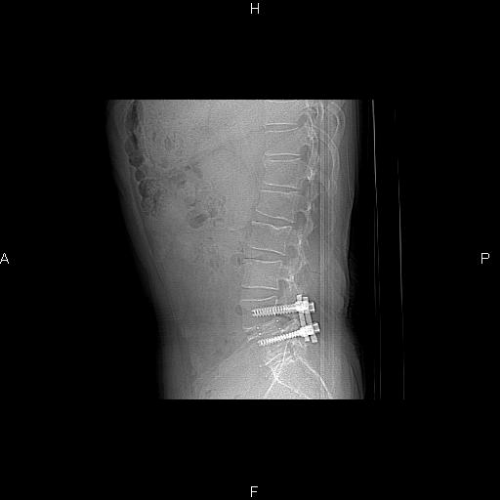

帮看看一二椎体什么情况

腰疼